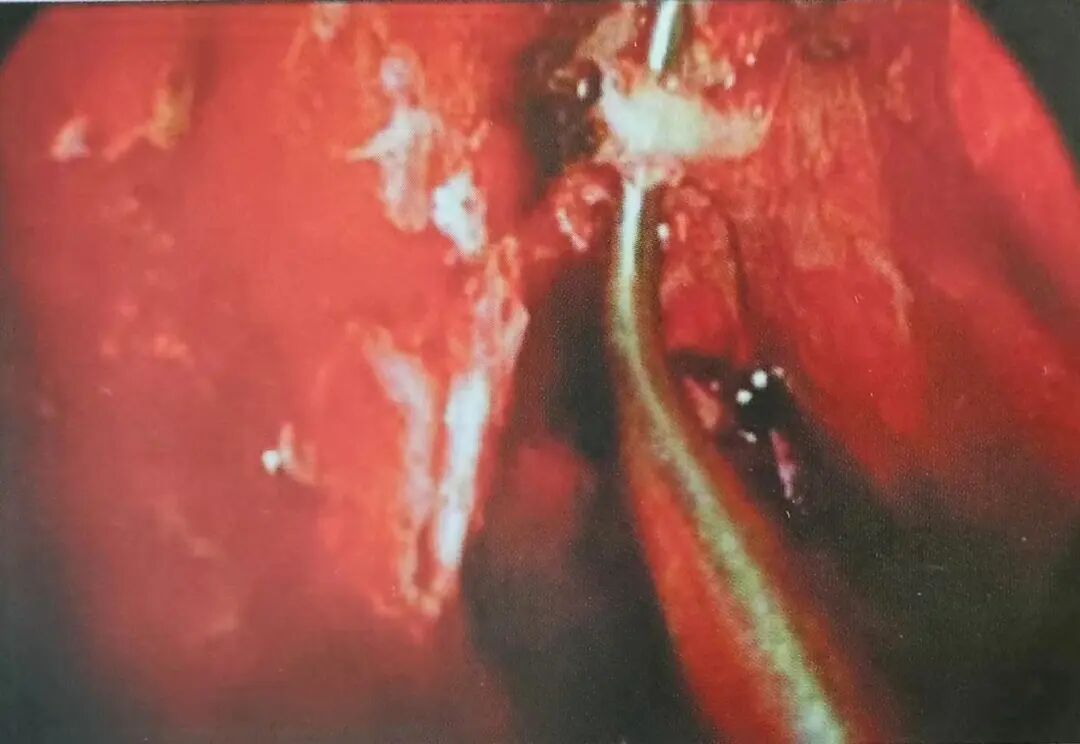

待鼻腔黏膜减充血后,进行鼻内镜下鼻腔检查。如果出血较迅猛,可先使用单极电凝暂时止血。为获得一个大的开窗,可使用反咬钳切除钩突。开窗自下界到达下鼻甲附着处,后界到达上颌窦后壁(图8)。一个大的开窗可为手术器械使用提供足够空间,同时也便于鼻腔外侧壁的骨膜下分离。使用剥离子从开窗的下后部位开始分离鼻腔外侧壁的黏膜骨膜(图9)。

图8左中鼻道开窗术后,开窗后部黏膜性骨膜自鼻腔外侧壁隆起(MT中鼻甲;PWA窦后壁)

怎么结扎血管面对鼻出血:7种关键血管结扎手术技巧!_https://www.jmylbn.com_新闻资讯_第9张

图9蝶腭动脉自上颌窦上后角显露